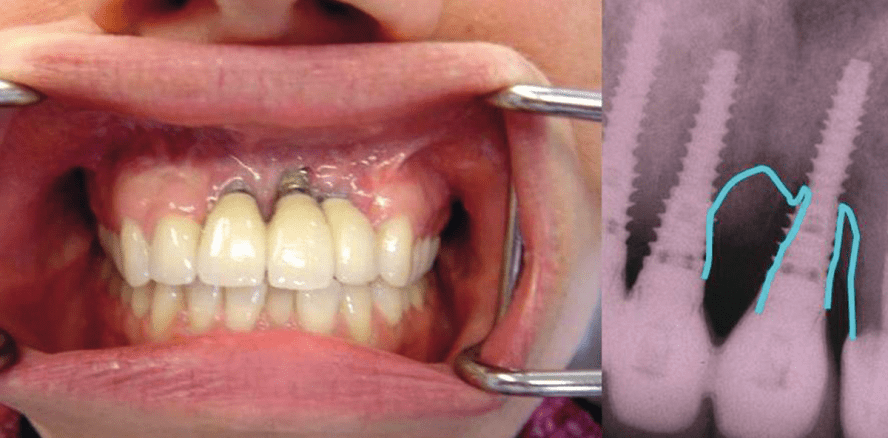

Versiegelungsmaterial // Periimplantitis (Abb. 1) zeichnet sich, dentaler Fachliteratur zufolge, als eines der wichtigsten und schwierigsten Themen der Implantologie ab. Für die Langzeiterfolge gilt es nun nach Möglich­keiten zu suchen, die Periimplantitis effektiv zu behandeln oder sogar zu verhindern, um ein dauerhaftes Verbleiben der Implantate zu ermöglichen.

Wie von Albrektsson et al. beschrieben, beginnt die Erkrankung der periimplantären Gewebe mit einer Mukositis, die später in einen progressiven, periimplantären Knochenverlust übergeht. Die Gründe für ein derartiges Krankheitsbild sind komplex und von verschiedenen Vermutungen begleitet, wobei schlechte Mundhygiene, der Mangel an fixierter Gingiva und/oder Überlastung der Implantate die Ursachen sein sollen. Allerdings werden diese auslösenden Faktoren von bekannten Implantologen infrage gestellt. Eine fehlende oder verminderte Breite der fixierten Gingiva muss nicht zwingend mit einer Gingivitis oder Periimplantitis zusammenhängen und eine funktionelle Überlastung kann auch nicht allein für den fortschreitenden Knochenverlust verantwortlich gemacht werden. Diese Tatsache legt nahe, dass weitere pathologische Einflüsse vorhanden sein müssen, die die Krankheit der ­Periimplantitis auslösen und unterhalten. Für die Behandlung der Periimplantitis werden verbesserte hygienische Maßnahmen, antibiotische und desinfizierende Einlagen in die periimplantären Taschen, Ultraschallkürettage und Laserbehandlungen der entzündeten Gewebe angeraten. Allerdings sollte das Hauptaugenmerk eher auf eine effektive Prävention als auf die Therapie gerichtet sein.